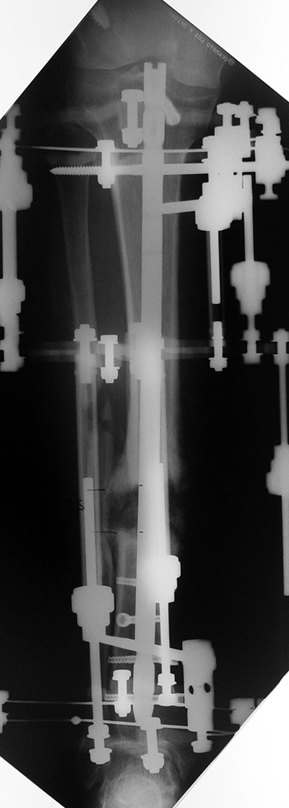

Recently, ilizarov techniques which is basis depend on distraction osteogenesis , bone segment transport or acute shortening after the resection at the site of pseudarthrosis combined with lengthening at another level of bone have been used. These treatment techniques may include some advantage for problems of infection, leg-length discrepancy, soft-tissue loss, and joint contracture.

Case 1